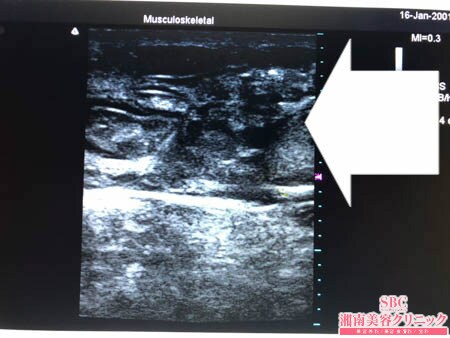

No.207874【脂肪吸引】【動画あり】湘南美容外科全ドクターの脂肪吸引最高責任者である竹田先生による脂肪吸引のフォトギャラリー!他院の再手術!細い二の腕ですらコンプレックスなのに太ももはもっと太いので絶対に脂肪吸引で細くしたい!術中3Dタッチビュー・右太もも後面

もともと硬くて線維質な皮下脂肪。

そこに1回目の脂肪吸引による

癒着と硬縮が追加され

難易度の高い脂肪吸引になりました。

しかし画像の通り

しっかりと根こそぎましたので

今回の脂肪吸引の結果には

間違いなくご満足いただけることでしょう。